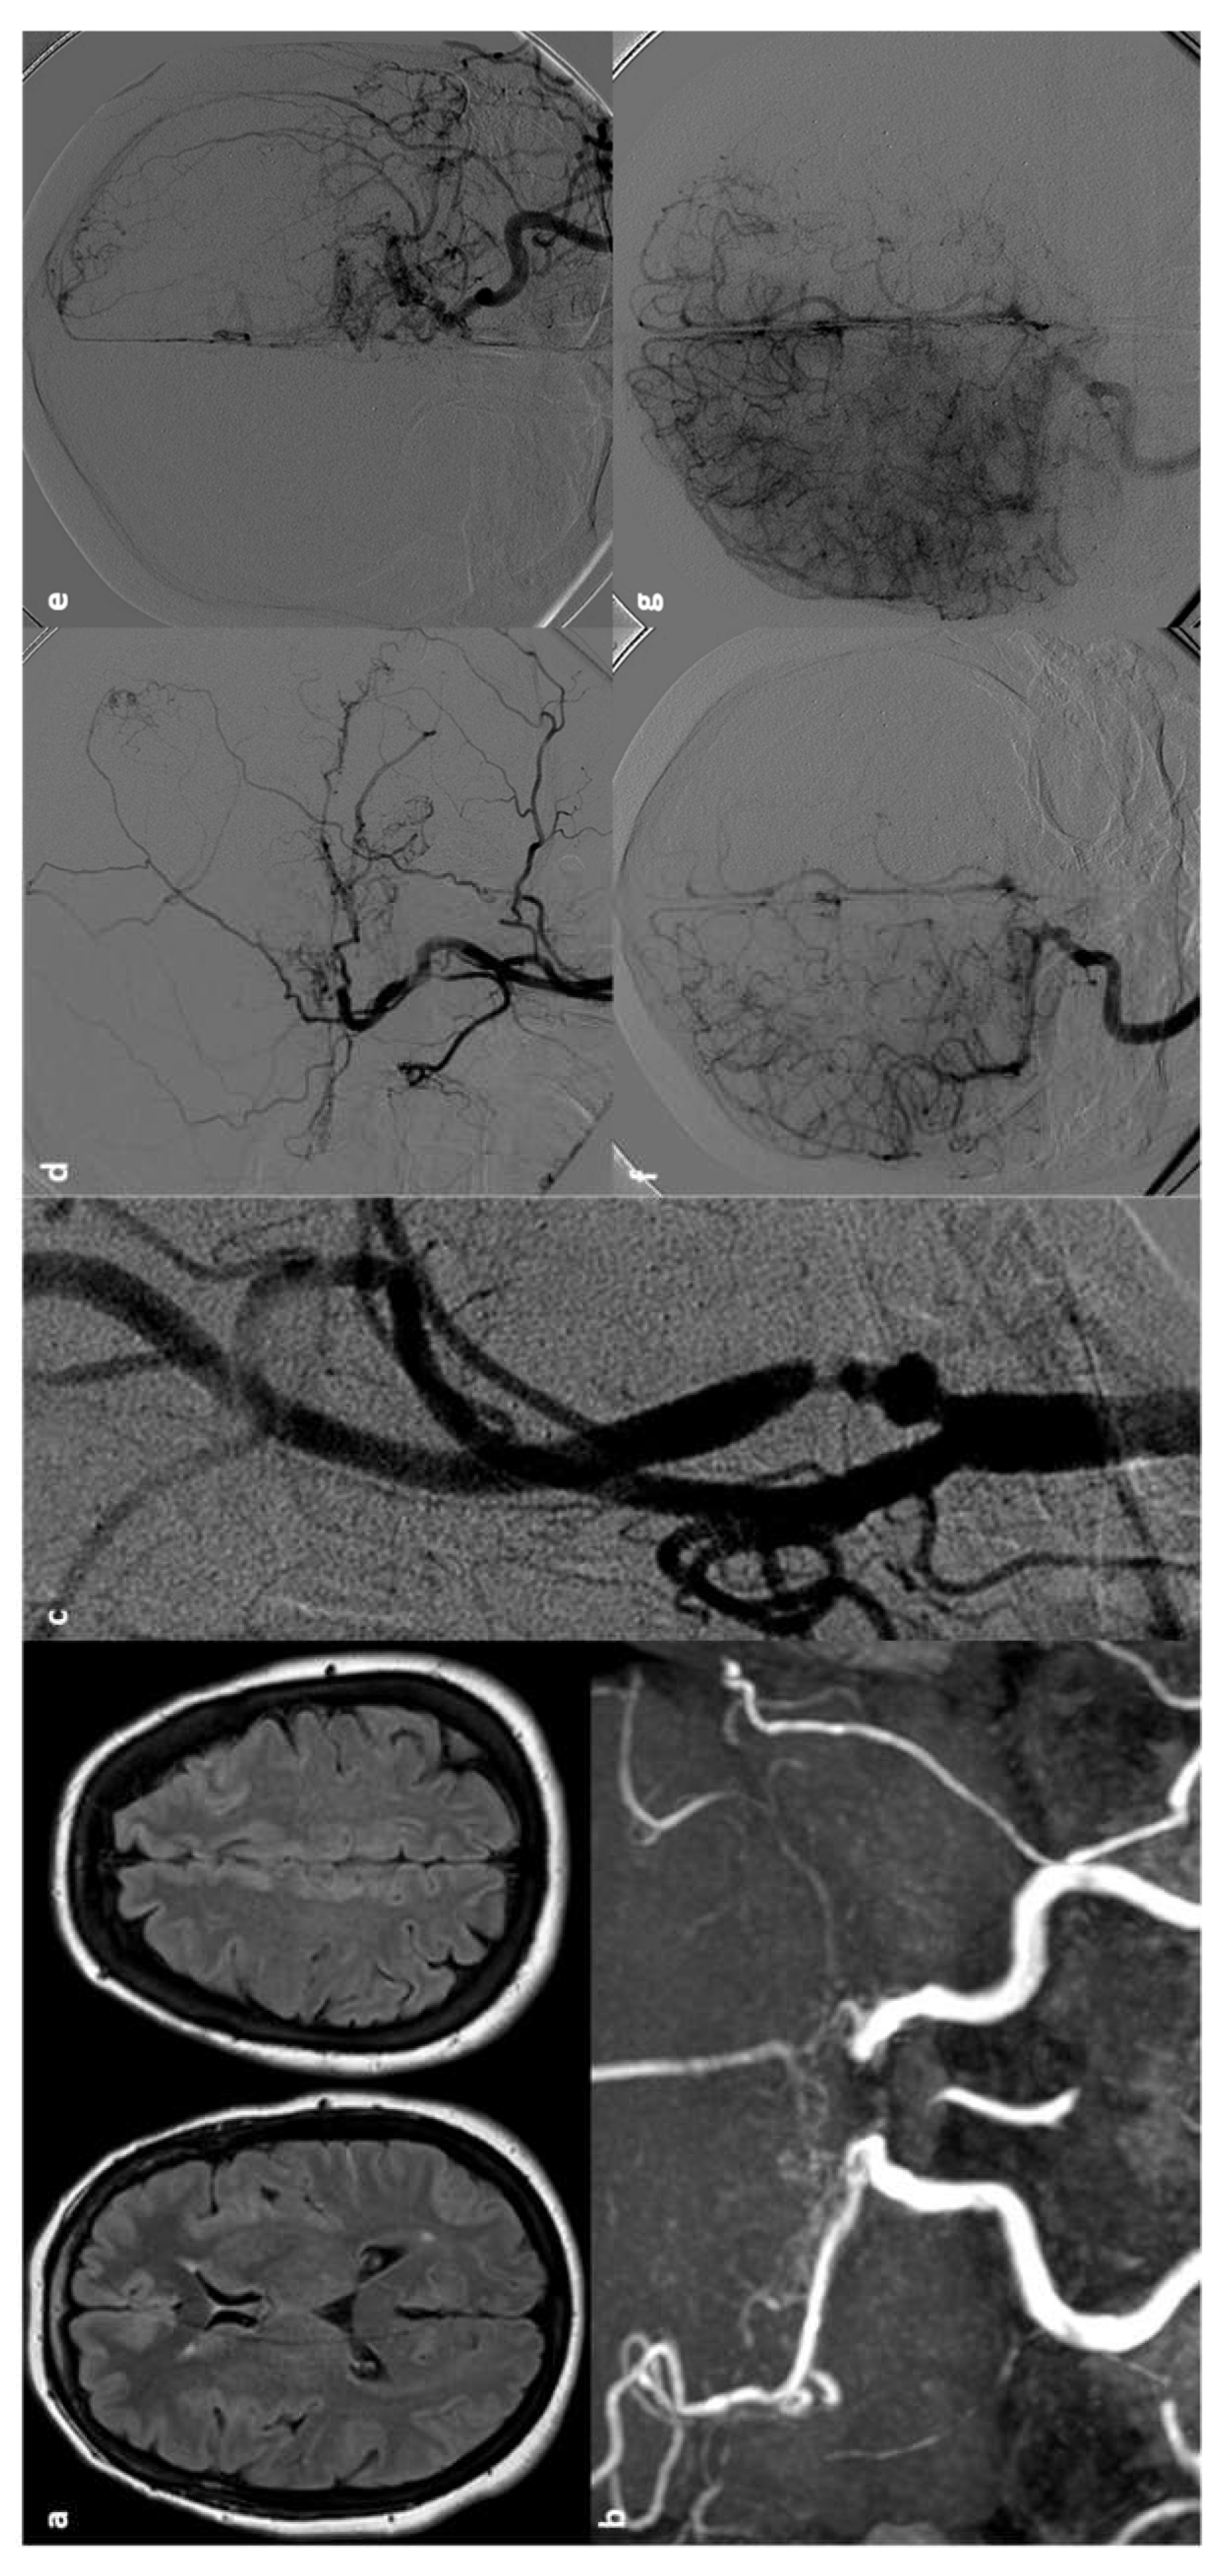

- Gallas S, Tuilier T, Ebrahiminia V, et al. Intracranial aneurysms in sickle cell disease: aneurysms characteristics and modalities of endovascular approach to treat these patients. J Neuroradiol 2019;47:221-6.

- Preul MC, Cendes F, Just N, et al. Intracranial aneurysms and sickle cell anemia: multiplicity and propensity for the vertebrobasilar Territory. Neurosurgery 1998;42:971–7.

- Nabavizadeh SA, Vossough A, Ichord RN, et al. Intracranial aneurysms in sickle cell anemia: clinical and imaging findings. J Neurointerv Surg 2016;8:434–40.

- Yao Z, Li J, He M, You C. Intracranial Aneurysm in Patients with Sickle Cell Disease: A Systematic Review. World Neurosurg. 2017 Sep;105:302-313. [CrossRef]

- Saini S, Speller-Brown B, Wyse E, Meier ER, Carpenter J, Fasano RM, et al. Unruptured intracranial aneurysms in children with sickle cell disease: analysis of 18 aneurysms in 5 patients. Neurosurgery. 2015;76:531-538.